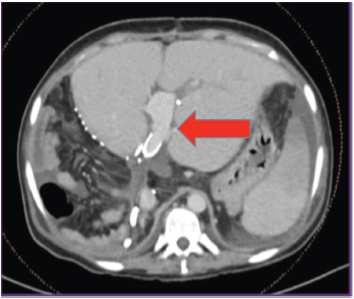

A 1250-g diseased liver was explanted (Figure 2), and the new graft from the left lobe of the patient’s brother (a 500-g living liver graft) was implanted. After completion of vascular anastomoses in the anhepatic phase, reperfusion was initiated after portal vein unclamping. At the end of the 7.5-hour surgery, Doppler ultrasonography confirmed normal flow in the portal vein, hepatic artery, and hepatic veins. The transplanted liver was clearly visualized by computed tomography-angiography (Figure 3).

Figure 2. Liver Tissue (1050 g) Removed From the Patient